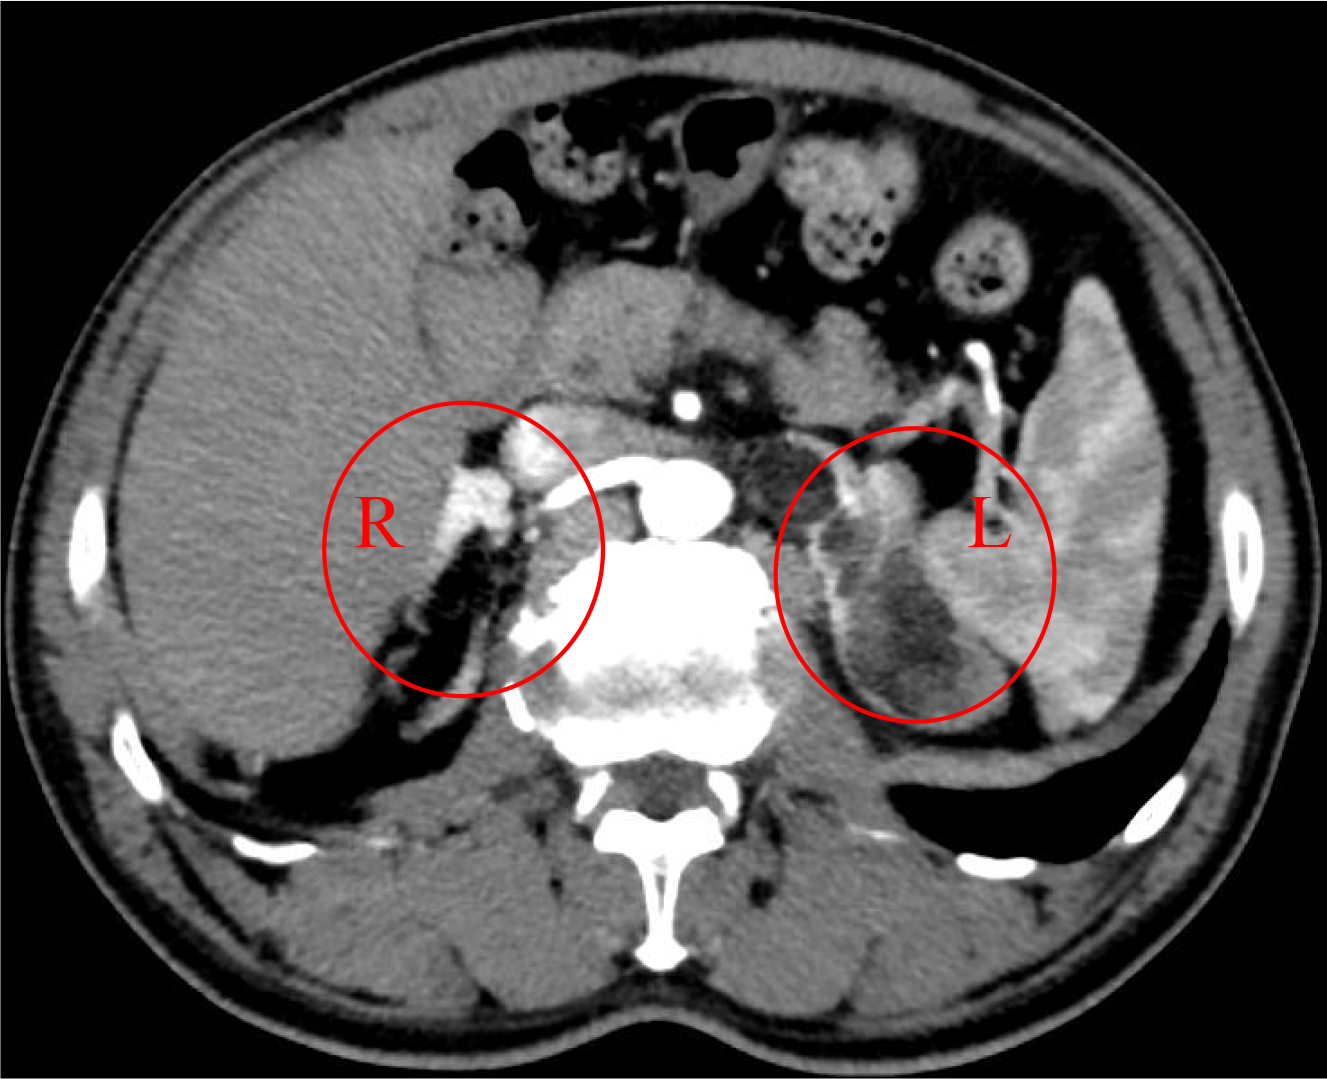

Subsequently, the patient independently sought medical attention at the First Affiliated Hospital, Zhejiang University School of Medicine. Renal tumor evaluation and computed tomography angiography (CTA) showed thickening of the right adrenal gland and multiple lesions in the left adrenal gland, meeting the criteria for adrenalectomy (Fig. 1). During consultation, the patient incidentally mentioned the recent development of cutaneous hyperpigmentation, prompting targeted endocrine evaluation. Therefore, the patient was admitted to the geriatric department for further assessment and management.

Fig. 1.

Renal tumor evaluation and computed tomography angiography (CTA). Thickening of the right adrenal gland and multiple lesions in the left adrenal gland (circles) were observed.